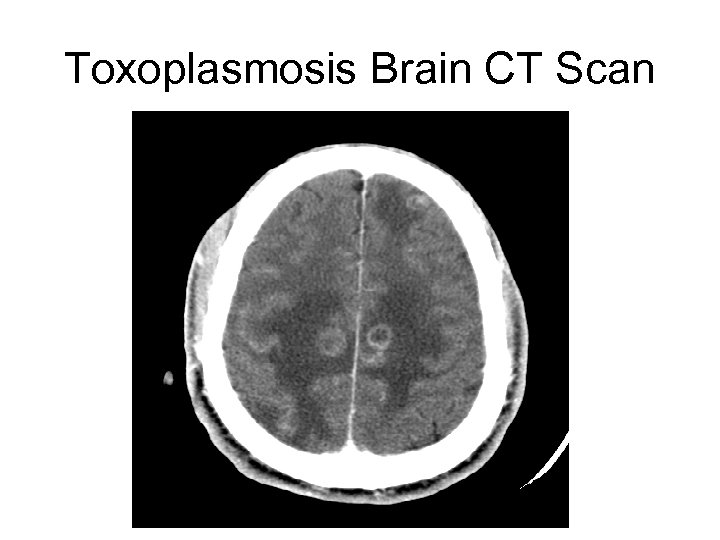

Toxoplasmosis Facts • Is caused by Toxoplasma gondii • Usual source is inadequately cooked meat and cats • Infection is usually acquired with no symptoms, it stays dormant and it grows when there is loss of cell mediated immune protection. • Seropositivity in Ethiopia reaches 80% • For a AIDS patient with CD 4 <100 mm 3 focal neurologic signs, cerebral toxoplasmosis is the most likely diagnosis

Treatment Considerations • The presentation is so characteristic that many guidelines suggest routine treatment for toxoplasmosis • A lack of response to such therapy (symptoms and MRI changes) within 1 -2 weeks indicates other possible conditions: – Central nervous system lymphoma – Tuberculoma – Cryptococcoma

Treatment Response • With empiric treatment for Toxoplasmosis, what should we expect? – Nearly 90% of patients will respond clinically within days of starting therapy – CT and MRI scans show improvement by 14 days following treatment initiation

Toxoplasmosis Brain CT Scan

Toxoplasmosis Treatment • Fansidar: 2 tabs bid x 2 days, then 1 tab qd (Ethiopia) • Alternative: Pyrimethamine 200 mg once, followed by • Pyrimethamine 50 -75 mg/day, plus • Sulfadiazine 1. 0 -1. 5 gm q 6 hrs, plus • Folinic acid 10 -20 mg/d* x 6 wks then half dose v Corticosteroids (dexamethasone 4 mg PO or IV q 6 hrs) used if cerebral edema present, and discontinued as soon as clinically feasible *Folinic acid needed with pyrimethamine, but expense limits use in Ethiopia